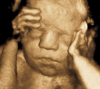

Diagnostic ultrasound (DUS) is, arguably, the most common technique used in obstetrical practice. From A mode, first described by Ian Donald for gynecology in the late 1950s, to B mode in the 1970s, real-time and gray-scale in the early 1980s, Doppler a little later, sophisticated color Doppler in the 1990s and three dimensional/four-dimensional ultrasound in the 2000s, DUS has not ceased to be closely associated with the practice of obstetrics. The latest innovation is the use of artificial intelligence which will, undoubtedly, take an increasing role in all aspects of our lives, including medicine and, specifically, obstetric ultrasound. In addition, in the future, new visualization methods may be developed, training methods expanded, and workflow and ergonomics improved.